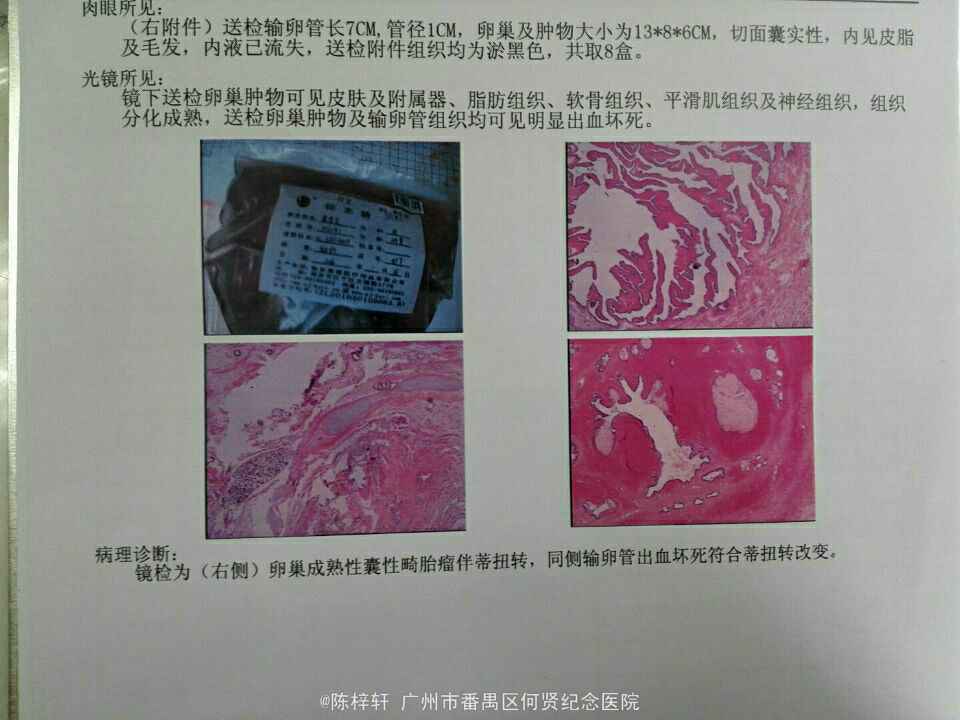

治疗

卵巢扭转的治疗方法是立即手术。手术旨在解除扭转、恢复卵巢血供和切除受影响的组织。手术可以通过以下方式进行:- 腹腔镜手术:通过几个小切口插入腹腔镜和手术器械进行手术。

- 开腹手术:在腹部切开一个较大的切口进行